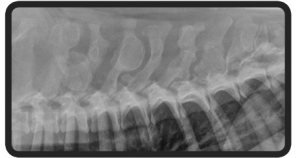

Veterinary teleradiology allows your hospital to partner with a radiologist who is board-certified with the ACVR. With a few mouse clicks, your diagnostic images (radiographs, CT, MRI) are submitted for interpretation, and you are able to offer your patients and clients the highest level of veterinary care.